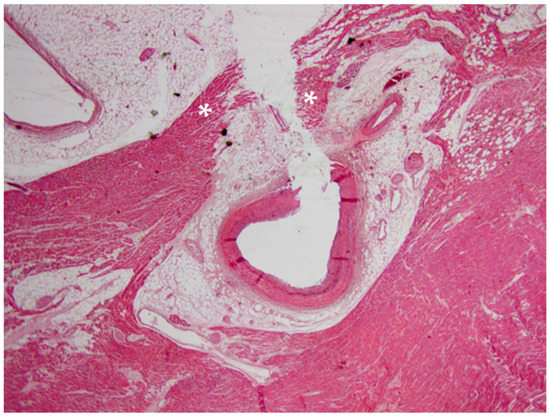

2. Case Report

6.1. Autopsy Findings